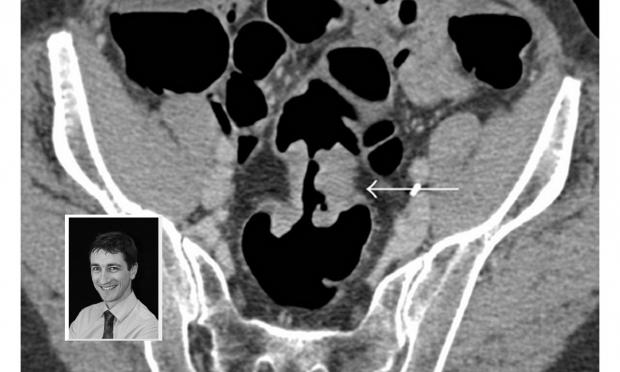

MJA Podcasts 2017 Episode 45: Virtual colonoscopy, with Prof Tom Sutherland

Volume 207, Issue 4: 21 August 2017. Professor Tom Sutherland is a radiologist on the executive of the Abdominal Radiology Group of Australia and New Zealand. He discusses CT colonography and its underuse in Australia. With MJA news and online editor, Cate Swannell.